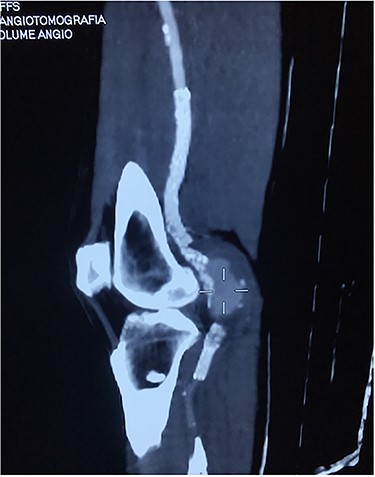

Angiotomography showing a fractured stent and pseudoaneurysm at the site of the fracture.